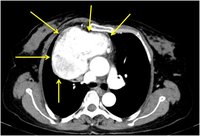

A 54-year-old female presented with history of a dry cough for the last 3 months. She has no history of breathlessness, chest pain, or fever. A CT of the thorax showed a large, intensely enhancing anterior mediastinal mass suspected to be mediastinal paraganglioma or thymoma by radiology.